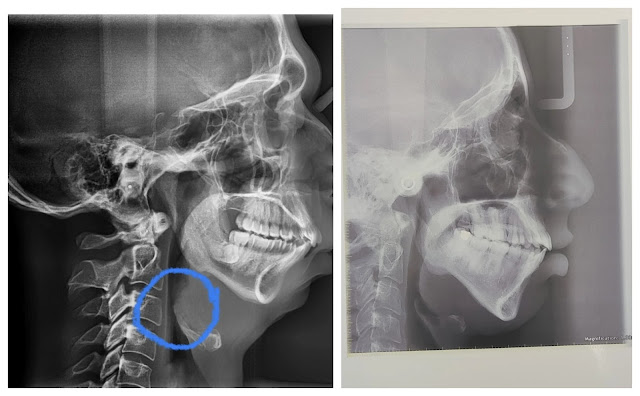

There is also a third variant of an adenoid face, but this one is extremely rare. Nonetheless, it should not be left out. This type is characterized by an ABSOLUTELY SMALL LOWER JAW (mandibular hypoplasia = underdevelopment, micrognathia). On the x-ray scans you can see why (+ notice the compensatory UPWARD HEAD-TILT):

The lower jaw of the patients above isn’t just pushed into downward and backward rotation by the growing maxilla, but it is extremely small at the same time. There can be multiple reasons behind it (all of them happening at a young age):

The first point is the temporomandibular joint itself and when rotation in this joint is anatomically no longer possible, the mandible will rotate in the second point. This one is located where the body of the mandible meets the mandibular ramus, as this place is the weakest point in our lower jaw. In most cases, you can find the second rotational point very easily, because it looks like a notch. This antegonial notch, along with the lengthening of apertura piriformis (see image below) and a prolonged midface, proves that the main cause of an adenoid face is in fact rotational growth of the maxilla and not only a lack of growth of the posterior part of the maxilla.

In the picture, you see an x-ray of my skull, and you can clearly identify the second point of rotation (you could also see it very well in some of the starving children):

My skull is the perfect tool for your learning. I want you to notice the slanted occlusal plane, optically enormous size of my nose, and protrusion of the alveolar process, which causes my lips to project forward and makes them more pronounced while making the chin look smaller. You see that

in my case, the mandible isn’t underdeveloped; it is just orientated differently. It's rotated. I do NOT have mandibular hypoplasia (micrognathia, small lower jaw), as I did eat tough food when I was a young child, but not frequently enough. Still, it stimulated the growth of my lower jaw, despite being insufficient to prevent the rotation in both of my jaws. Later, I will talk more in detail about the nose issue depicted here. See the difference in the soft tissues of my face after I rotated both of the jaws (so that the occlusal plane is horizontal) in the second image above.